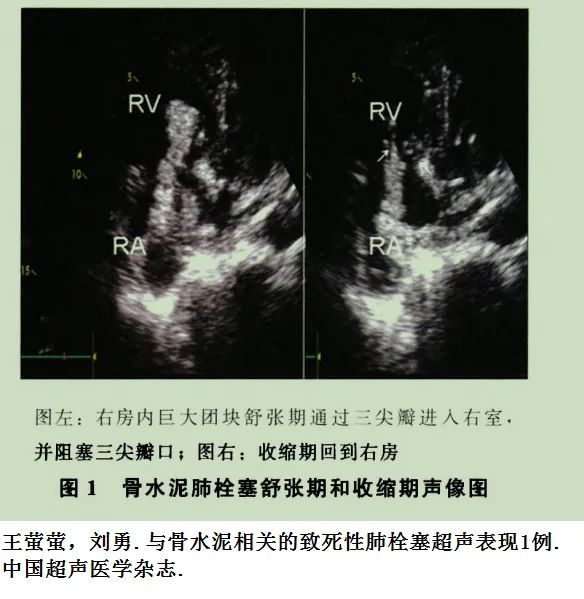

患者骨科手术后呼吸困难,急诊肺动脉CTA检查,增强CT未见充盈缺损,肺血栓形成目前不考虑。但是患者为什么出现呼吸困难,脂肪栓塞?看看CT平扫,有什么发现?乍一看,还以为是纵隔淋巴结或血管钙化,说不定还会随口给家属一句“是钙化,不用处理,没事”。结合病史,仔细一看,原来是奇葩骨水泥肺栓塞。事可大了!双肺多发的骨水泥肺栓塞。这种情况下,看增强CT,造影剂反而会掩盖肺栓塞。胸片:胸片也能诊断骨水泥肺栓塞。术前几乎都要常规做胸片,术后胸片发现新增的条状、树枝状高密度阴影,结合临床表现,也可诊断骨水泥肺栓塞。超声:心脏彩超可发现心脏内的骨水泥栓子,床旁超声也可搞定,还可以同时评价心脏功能。